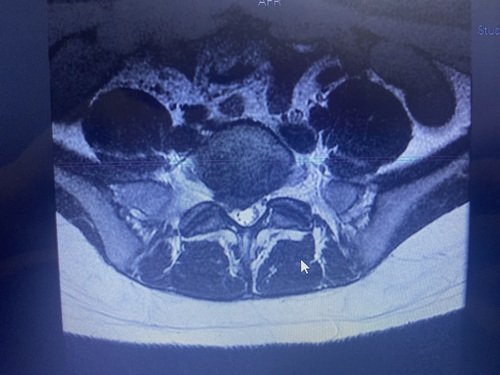

Olá, sou a Thainar, tenho 24 anos. Estou desde o dia 04/10/2023 em casa por complicações na minha coluna. Uma hérnia de disco aumentou bastante na minha coluna, gerando uma extrusão onde aperta o meu nervo ciático e acabou inflamando o nervo.

Desde quarta os remédios (que não são poucos que estou tomando e nem baratos) não estão mais ajudando e estou de cama. Pois a dor é terrível (começa a dor na lombar, queima e da pontada até a ponta do pé). E não tenho outra forma de resolver a não ser passando pela cirurgia.